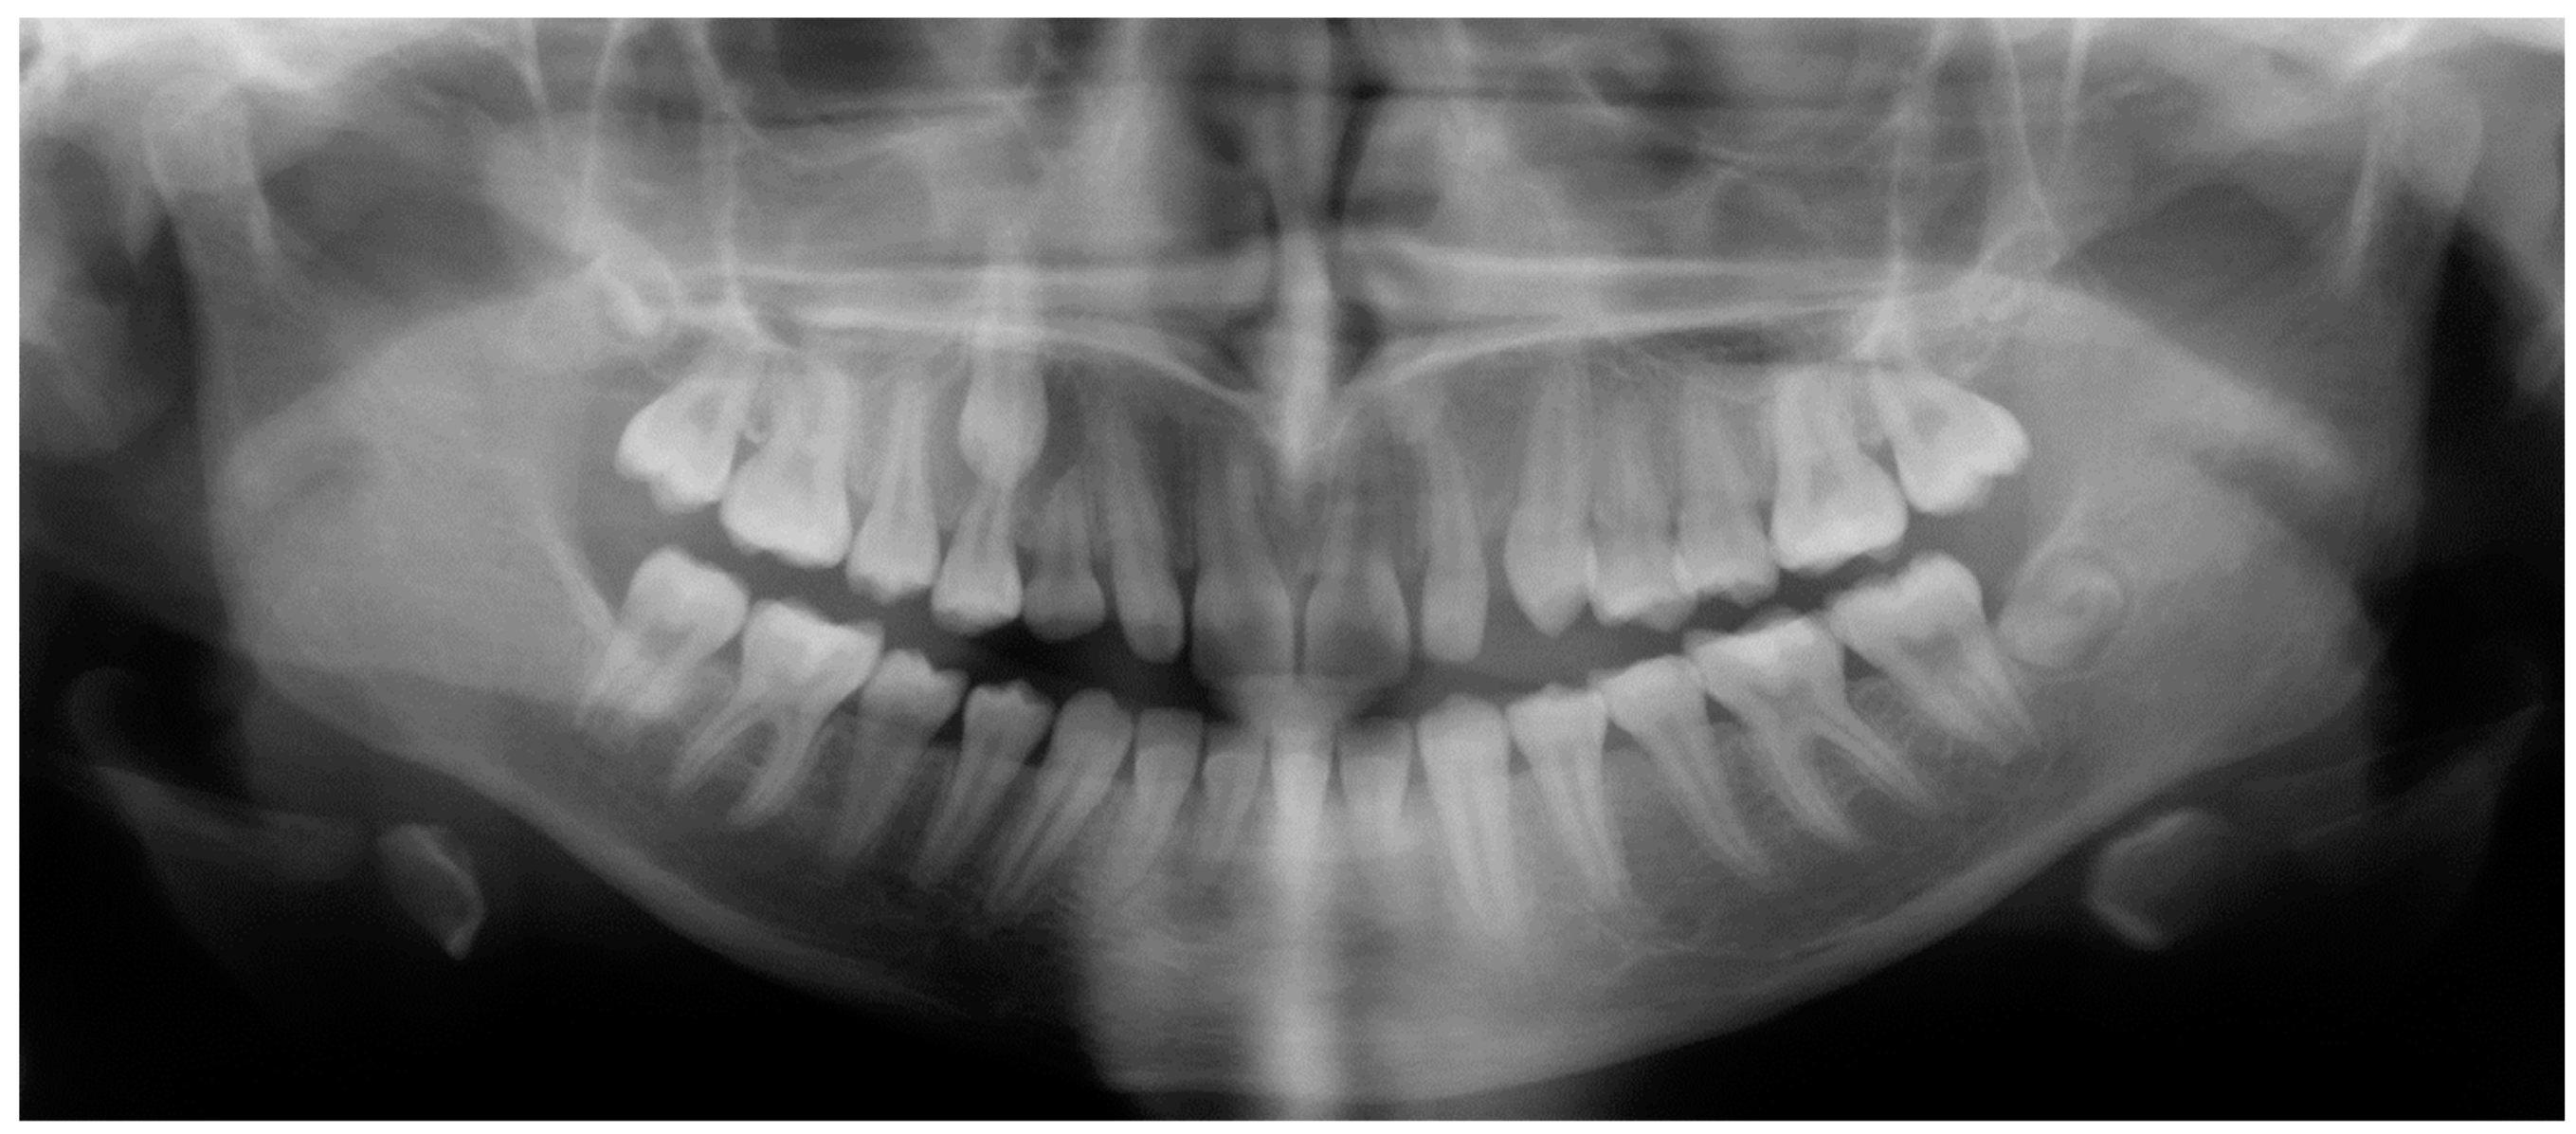

- Assessment of an ankylosed and submerged primary tooth. Due to limitations of panoramic radiography, objects located outside of the focal trough may not be well visualized. In addition, it may be difficult in some cases to visualize objects that are located within the focal trough. Figure 16 presents an example of a conventional 2D panoramic radiograph in which it was impossible to visualize an ankylosed and submerged primary maxillary left second molar for a child who was 11 years of age. There are two findings that can be seen on the conventional panoramic radiograph: a transposition between the maxillary right canine and first premolar, and a missing maxillary left first premolar. However, the impacted primary molar in the upper left quadrant is not depicted on the conventional panoramic radiograph in Figure 16. After acquisition of CBCT, which was made on the same day the 2D panoramic radiograph was taken, it was possible to see the primary tooth. Figure 17 shows a panoramic view derived from the CBCT volume which shows the ankylosed and submerged primary maxillary left second molar. This tooth can also be seen in the CBCT volume rendering in Figure 18. Interestingly, the patient had another CBCT scan taken approximately three years earlier when the child was 8 years of age. The earlier scan explained the etiology for the problems in the upper left quadrant. The earlier CBCT, displayed in Figure 19, shows that the primary maxillary left second molar was fully erupted and present in the mouth. After the primary tooth became ankylosed, it gradually became severely infraoccluded and then became completely submerged. Meanwhile, the adjacent permanent maxillary left first molar drifted mesially due to lack of space mesial to the tooth, and at the same time the ankylosed primary molar obstructed the eruption of its succedaneous premolar.